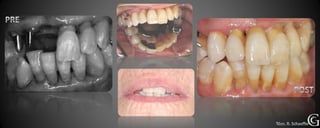

Prótesis Fija Convencional

Restauraciones periféricas totales “coronas”

Las coronas son restauraciones que involucran la totalidad del

diente, confeccionadas fuera de la boca (indirectas totales) que

luego son adheridas al diente en tratamiento. Pueden ser de

diversos materiales, cerámicas, composite y/o metálicas.

Técn. R. Schaeffer

Prótesis Fija Convencional Restauracionesperiféricas totales “coronas” Las coronas son restauraciones que involucran la totalidad del diente, confeccionadas fuera de la boca (indirectas totales) que luego son adheridas al diente en tratamiento. Pueden ser de diversos materiales, cerámicas, composite y/o metálicas.